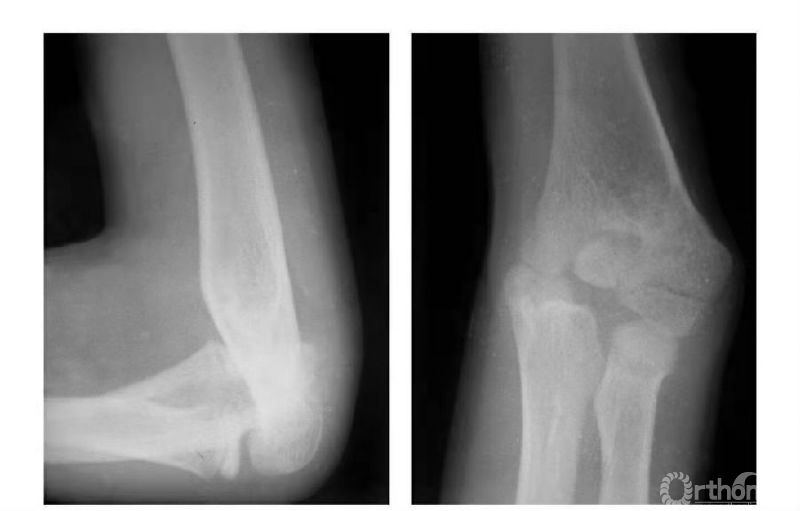

例2:肱骨内髁滑车关节面骨折,骨块嵌夹在尺肱关节间,且有翻转现象(图5)。

图5

例4:肱骨内髁滑车骨折,且骨块内移,致骨骺因损伤而早闭,并形成肘内翻畸形(图7)。

图7